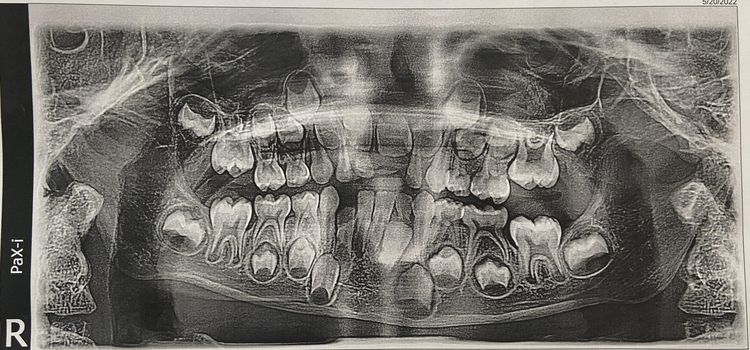

Рентген шестилетнего ребенка: зубы молочные и постоянные стоят рядами, как солдаты в строю. Скоро выпадут - и начнется новая глава.